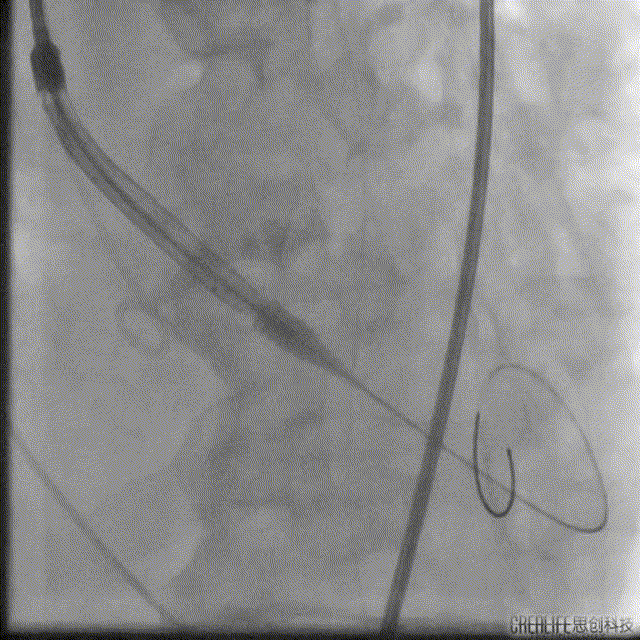

解剖上,这个患者虽然是右无融合的二叶瓣,但是右窦发育较小,形态上接近0型二叶瓣,瓣上钙化中,且集中在左窦,接近左右瓣叶联合部。瓣环及流出道平面较大,而瓣上结构较小,瓣叶联合部距离只有26,这种情况下只能考虑根据瓣上结构进行选择瓣膜。目标瓣膜为26号,为了避免破坏瓣上结构,我们选择26瓣膜的下限20号瓣膜进行与扩张。因为主动脉弓和升主动脉角度问题,没有选择plus。20球囊扩张可以看到左窦钙化很硬,右无联合可以推开,没有反流,故选择26号瓣膜,高位释放。释放后瓣膜下滑到标准位,有明显的腰,故用20球囊进行后扩展。最后造影虽然有中度瓣周漏,但是考虑患者狭窄解除,且升主动脉人工血管限制了瓣膜的流出端,未再行瓣中瓣。术中撤除ECMO,辅助循环约1小时。

Numed20后扩